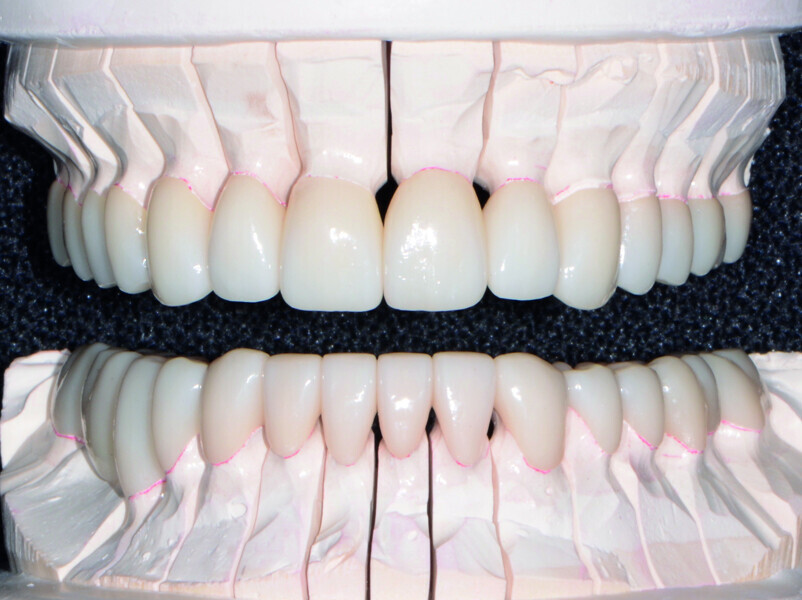

Restoring function and aesthetics with monolithic zirconia restorations